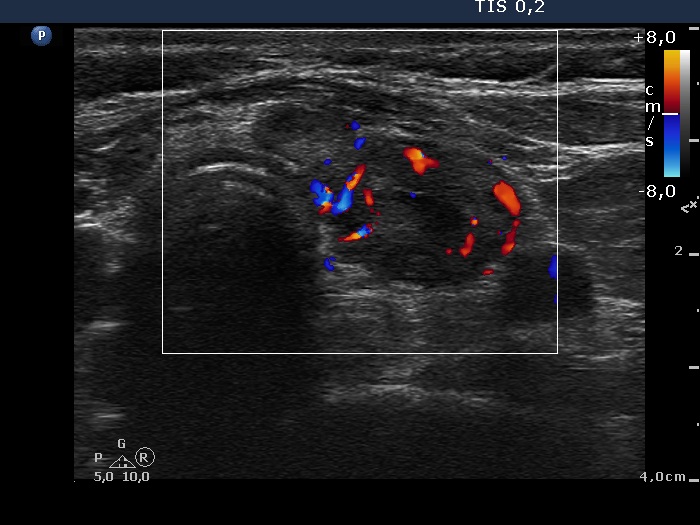

First examination - before surgery (first and second rows of images)

Ultrasonography. Both lobes were hypoechogenic and contained several hypoechogenic areas do not corresponding to nodules. The echogenicity index was 20%. The vascularization was a bit increased.